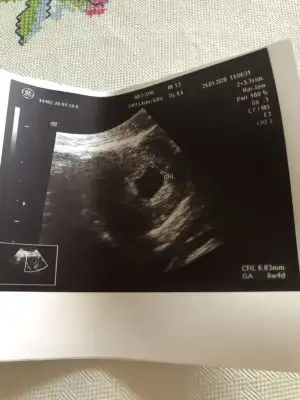

Çok teşekkür ederim evet işaretli olan yer geçen hafta görmüştük canım kalp atışını zaten bu haftada izledikNee guzel masallah . Isaretli yer bebek mi acaba net goremedim de merak ettim kalp atisi ile ilgili birsey dedi mi

Nee guzel masallah . Isaretli yer bebek mi acaba net goremedim de merak ettim kalp atisi ile ilgili birsey dedi miŞimdi geldim hastaneden bebişim sağlıklı sorun yok dedi ilk baştan beri 1 hafta geriden geliyoruz geç döllenme dedi kan tahlili yaptı idrar yolu enfeksiyon yok dedi ama yine de bi kültür yapalım dedi trombositlerin güzel iğneye devam edeceğiz dedi folik asit yarım yarım iç dedi bu ara folik asitle ilgili hiç hoş şeyler duymuyorum dedi sonrada folbiol değil de GEBYFOLL başlayalım dedi bizden bu kadar